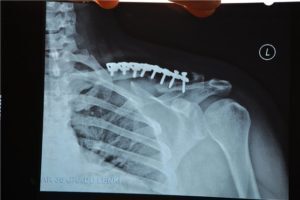

Намедни решили меня пранкеры разыграть. Шёл я к родителям вечерком. Нужно было скрепить трубы для навеса. С болтами не стал заморачиваться - купил шпильку метровую толщиной с палец с целью порезать. А путь мой пролегал мимо старого кладбища, где и выскочил на меня странный чувак в маске и лохмотьях, ну и мой инстинкт самосохранения нанес удар этой шпилькой прямо по пранкеру. Благо не по голове, а по плечу. Короче, паренёк знатно прихуел, хочу вам сказать, но ломанули они довольно резво от меня - наверное решили, что буду их добивать. Блин, вот даже не мог подумать, что у нас в городке заведутся эти деятели.